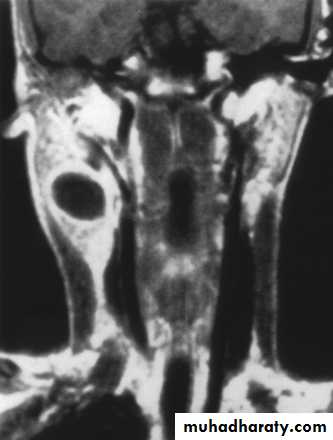

Vascular Tumors

Lymphangiomas and hemangiomasUsually within 1st year of life

Hemangiomas often resolve spontaneously, while lymphangiomas remain unchanged

CT/MRI may help define extent of disease

46

TreatmentLymphangioma – surgical excision for easily accessible or lesions affecting vital functions; recurrence is common

Hemangiomas – surgical excision reserved for those with rapid growth involving vital structures or associated thrombocytopenia that fails medical therapy (steroids, interferon)

47

Vascular Tumors (lymphangioma)

48